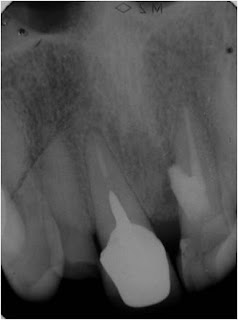

- Dente 25 com sensibilidade a percussão vertical / horizontal

- Presença de Bolsa Periodontal

- Presença de Fístula

- Tratamento Endodôntico Realizado há aproximadamente 05 anos

Com esses dados clínicos e a radiografia de rastreamento da fístula realizada, como vc avaliaria este caso:

1 - Diagnóstico: Fratura; Plano de Tratamento:Exodontia ;

2 - Diagnóstico: Rarefação Óssea Periapical; Plano de Tratamento: Remoção de Prótese, Núcleo e Retratamento;

3 - Diagnóstico: Rarefação Óssea Periapical; Plano de Tratamento: Cirurgia Paraendodôntica;

Façam seus comentários...daqui alguns dias postaremos o desfecho dessa história.